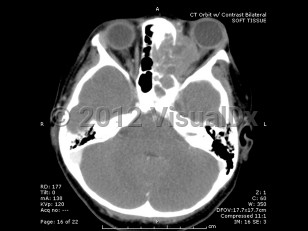

Orbital rhabdomyosarcoma - External and Internal Eye

Rhabdomyosarcoma is a rare childhood cancer that affects approximately 350 children per year in the United States, with 10% of cases involving the orbit. Rhabdomyosarcoma is the most common primary orbital tumor in childhood. Patients usually present between 5 and 10 years of age, with boys having a higher incidence than girls.

Proptosis is the most common presenting sign and may develop over the course of just a few days or a month. Often there is a history of recent trauma upon presentation of the tumor, which may lead to confusion with the diagnosis. Orbital rhabdomyosarcoma sometimes presents with strabismus or as a localized eyelid or conjunctival mass.